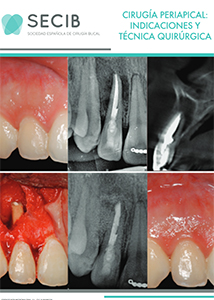

La cirugía periapical, también conocida como apicectomía, consiste en eliminar el tejido inflamado o infectado que rodea el ápice (extremo) de la raíz de un diente. Es una intervención precisa que permite conservar piezas dentales que de otro modo serían extraídas.

Se recurre a esta técnica cuando persiste una infección tras una endodoncia, o cuando hay quistes, granulomas, perforaciones o fracturas radiculares que no pueden tratarse por vía convencional.

¿Cómo se realiza una apicectomía?

Nuestro tratamiento de apicectomía en Valencia sigue una secuencia precisa, basada en la evidencia científica:

- Anestesia local para una cirugía sin dolor.

- Incisión y acceso óseo a la zona periapical.

- Limpieza quirúrgica del tejido inflamado o infectado.

- Resección del ápice radicular.

- Sellado retrógrado del conducto con materiales biocompatibles.

- Sutura y control postoperatorio.